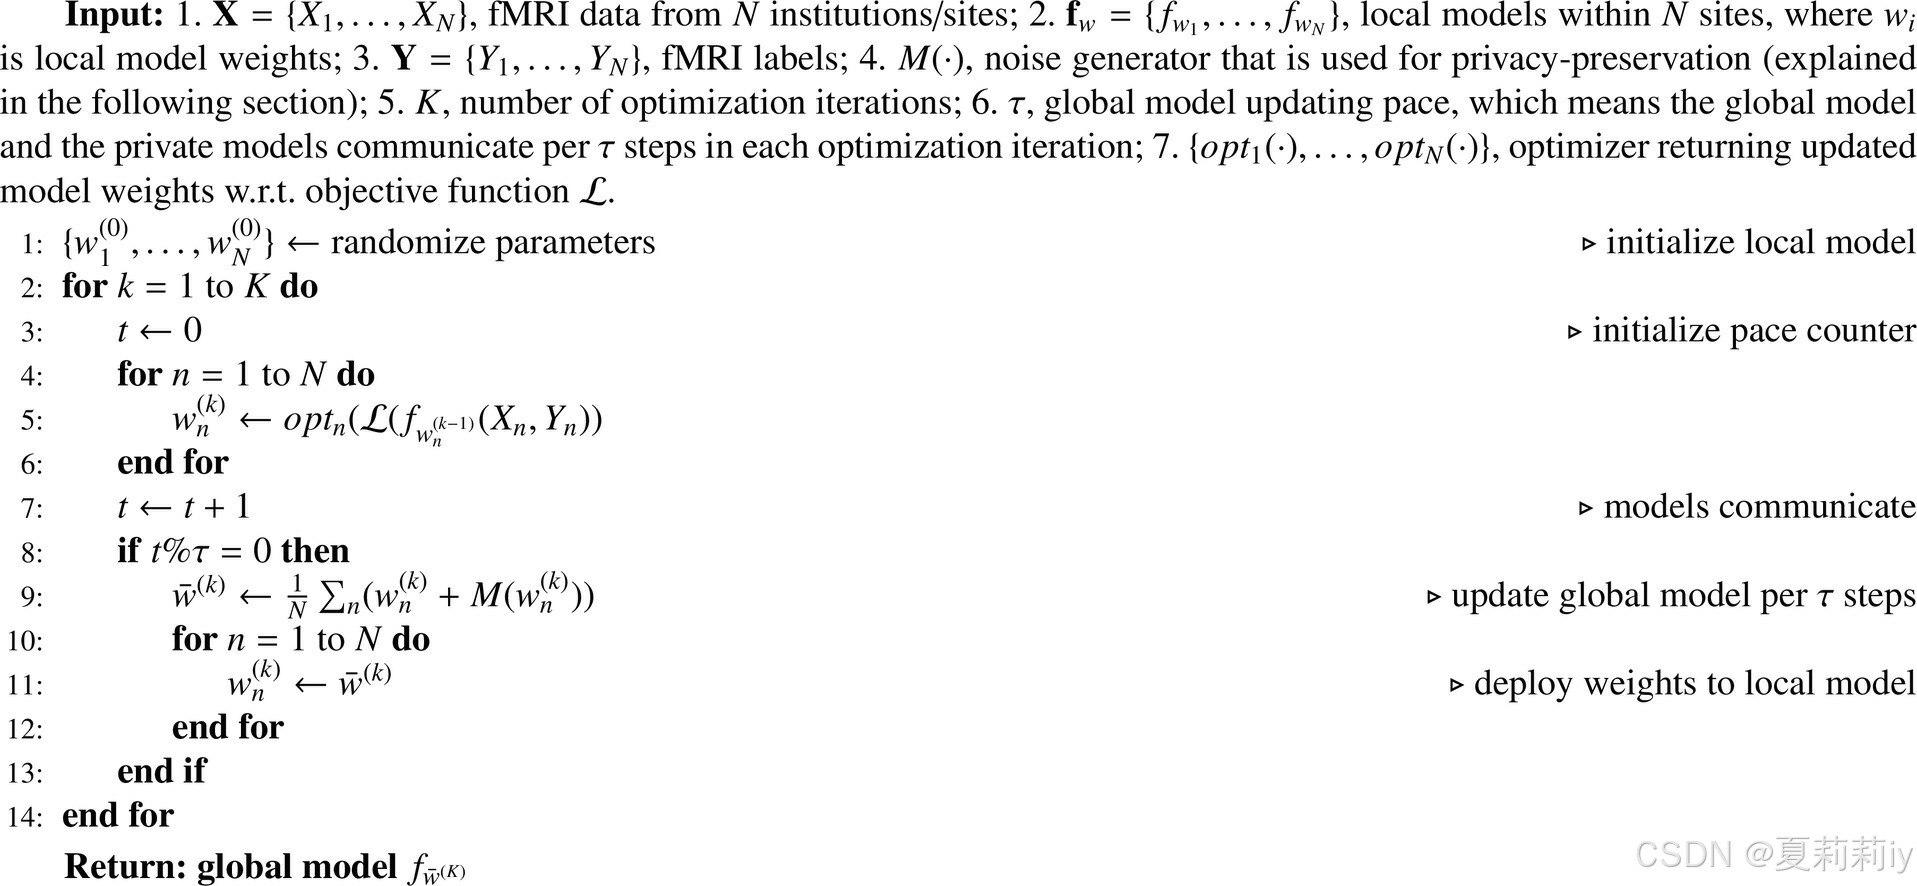

(1)Problem definition

①Data in -th site is denoted by matrix

② sites:

with institution owning private fMRI data

③Feature space is noted by (extracted fMRI feature), label space is

(diagnosis or phenotype needing predict) and sample ID space is represented by

④Data distribution:

⑤FL:

(2)Privacy-preserving decentralized training

①Cross entropy loss in this FL:

where denotes the label of the

-th subject in the

-th site,

, and

is the predicted probability

②Training process:

(3)Randomized mechanism for privacy protection

④Gaussian Mechanism: adding noise to

They employ Laplace Distribution with scale :

and , the

noise will be add to

, the difference privacy is

(作者只用了一个参数咩~)。然后他们为了简化讨论假定灵敏度

为1???这能假定吗?这不是两个数据集间的差异吗。我猜测作者是在说两个站点间参数的差异为1?